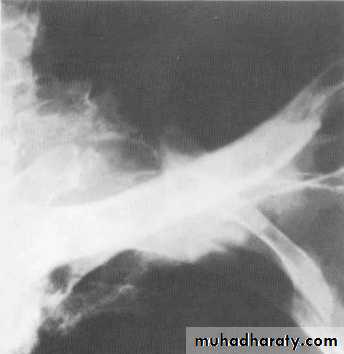

Massive pleural effusion with mediastinal shift to the left.

(A) Chest radiograph(B) CT coronal reconstruction. A massive effusion displaces the mediastinum to the left. CT shows the important pleural effusion together with the enhanced atelectatic left lung.

Note also the depression of the right hemidiaphragm (arrows).